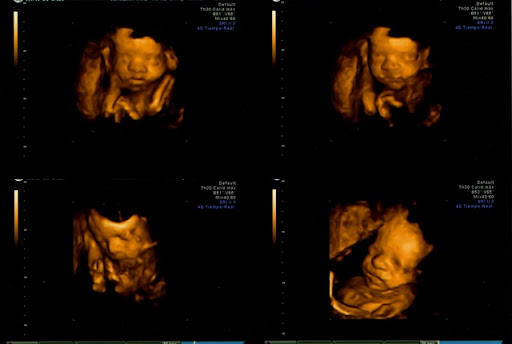

Pues nada, ahora os cuento cómo ha ido la 4D. Al principio pensamos que no íbamos a poder ver nada y que tendríamos que repetirla de nuevo, porque el muchacho estaba hoy justamente mirando hacia mi espalda. Al final, ha sido difícil y ha requerido paciencia y mucho meneo para que se moviera, pero lo hemos conseguido. Además el gine se ha portado genial y no ha ido ni corriendo ni nada... Aquí os dejo las fotos. Sólo deciros que hemos disfrutado muchísimo viendo a Álvaro. Cómo se movía, los gesto que hacía... Ha sido genial.

Bueno, buenas noches a todas y ahí os dejo las fotillos. Espero que no salgan muy grandes.

01.jpg02.jpg03.jpg04.jpg

encontradoraaaaaaaa dios mi oque bien se ve, esta guapisimo. salen muuy bien y claritas todas las fotos y ea y otra foto de la churra jejejej que bien que se ve. felicidades por tu hombresito guapeton.

Encontradora, ¡qué bien se ve! Qué envidia, ojalá el lunes vea a mi peque así.

Encontradora Que fotos tan bonitas!! Que bien se le ve!! ¿Verdad que es muy emocionante? Ya sabemos mas o menos la carita de nuestro bebé ¡Es genial! Enhorabuena!!